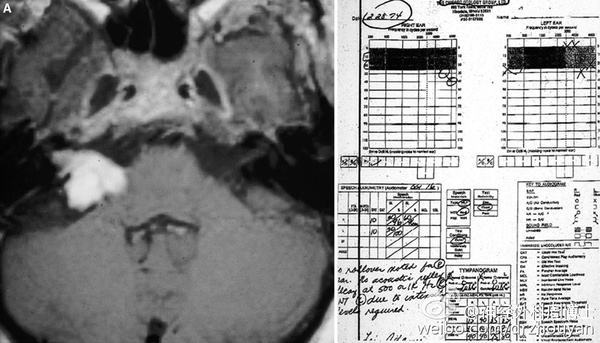

Case 5

该患者肿瘤体积较大,术后听力保留。A. 术前MRI和电测听结果,语言辨别值为96%。B. 术后MRI和电测听结果,语言辨别值为100%。